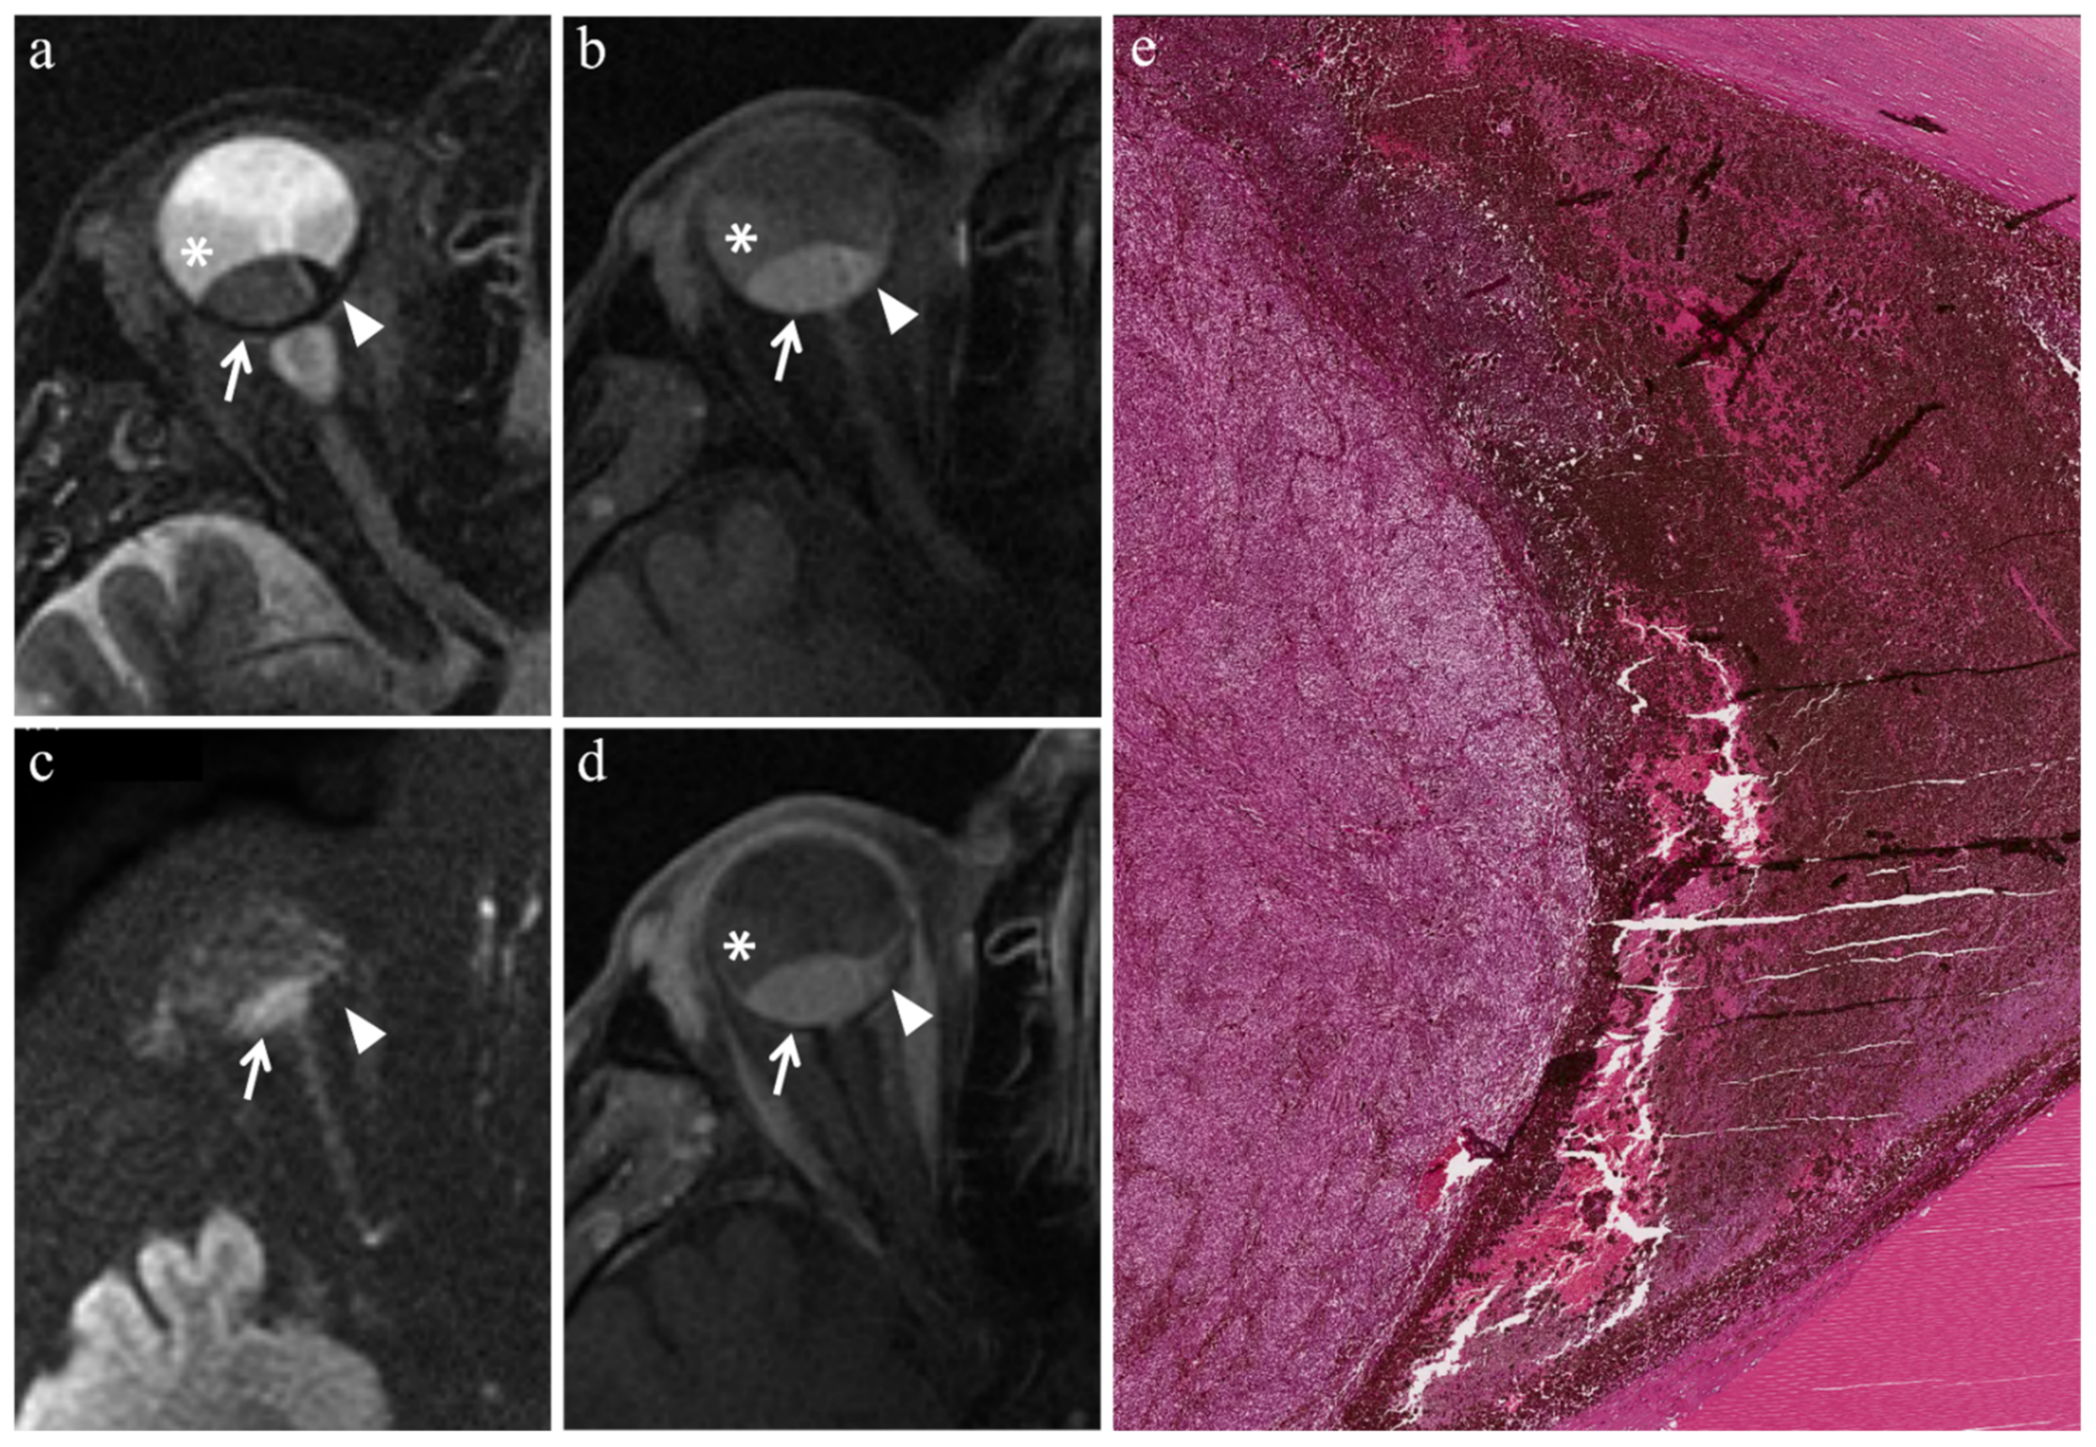

| Patient | Histologic Type | Radiation-Induced Necrosis Histology MRI | Fibrosis Histology MRI | Viable Tumor Tissue Histology MRI | |||

|---|---|---|---|---|---|---|---|

| 1 | Epithelioid cell | - | - | - | - | Yes | Yes |

| 2 | Necrosis without viable tumor tissue | Yes | Yes | - | - | - | - |

| 3 | Spindle cell | Yes | Yes | - | - | Yes | Yes |

| 4 | Epithelioid cell | Yes | Yes | - | - | Yes | Yes |

| 5 | Spindle cell | - | - | - | - | Yes | Yes |

| 6 | Fibrotic scar without viable tumor tissue | - | - | Yes | Yes | - | - |

| 7 | Spindle cell | Yes | Yes | - | - | Yes | Yes |

| 8 | Mixed cell type | - | - | - | - | Yes | Yes |

| 9 | Mixed cell type | Yes | - | - | - | Yes | Yes |

| MR Finding | T2 | T1 | Gd-T1 | DWI |

|---|---|---|---|---|

| Radiation-induced necrosis | ![]() Low signal | ![]() High signal | ![]() No enhancement | ![]() Low signal |

| Fibrosis | ![]() Low signal | ![]() Intermediate signal | ![]() Moderate enhancement | ![]() Low signal |

| Viable tumor tissue, pigmented melanoma | ![]() Low signal | ![]() High signal | ![]() Enhancement of viable tissue | ![]() High signal |

| Viable tumor tissue, poorly pigmented melanoma | ![]() Intermediate signal | ![]() Intermediate signal | ![]() Enhancement of viable tissue | ![]() High signal |

low signal;

intermediate signal;

high signal;

no enhancement;

enhancement of the viable tissue.| MR Finding | T2 | T1 | Gd-T1 | DWI |